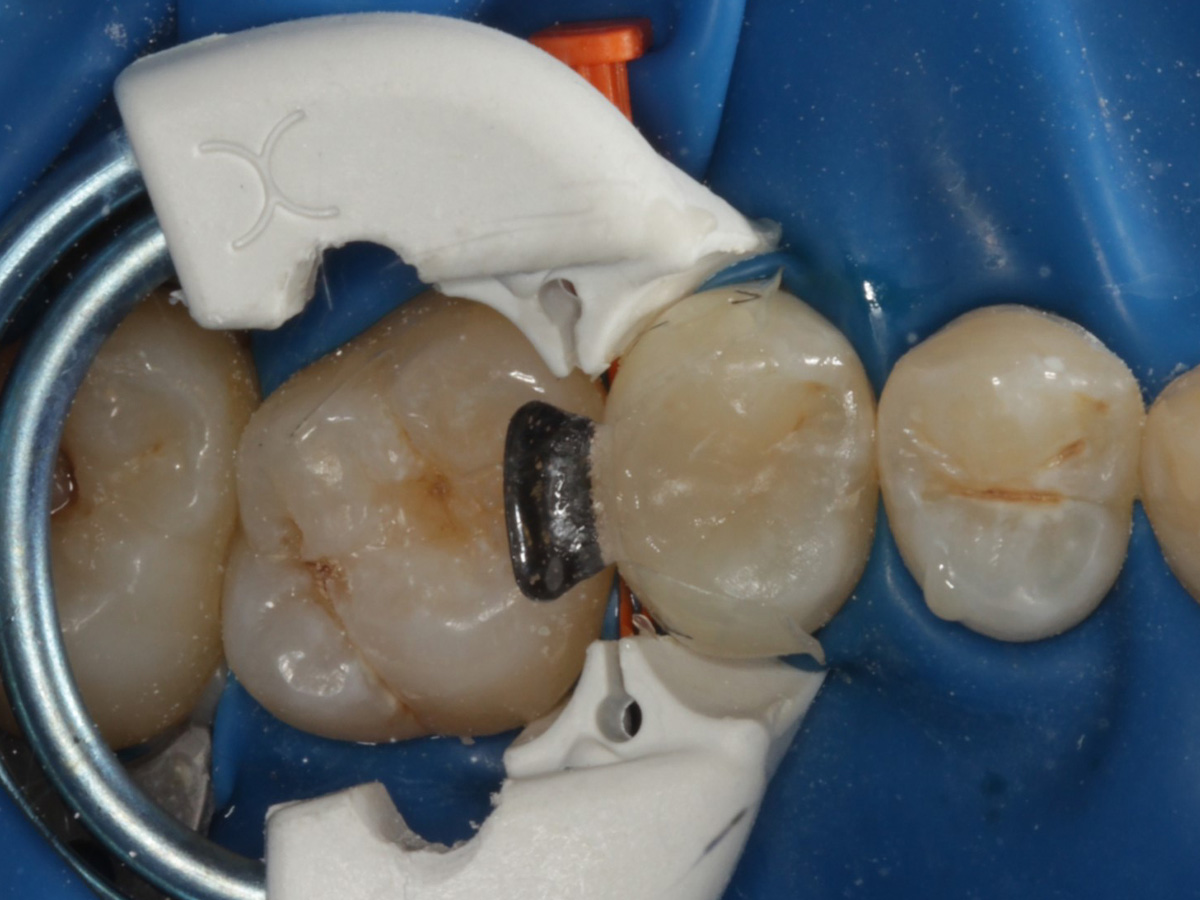

Abbildung 3

Quadrantenisolierung mit Kofferdam (x-heavy)

Abbildung 4

Schutz des Nachbarzahnes und des Kofferdams mit wiederverwandter Bioclear Biofit Matrize (gereinigt und sterilisiert); Separation zur Applikation der Matrize mit Heidemannspatel